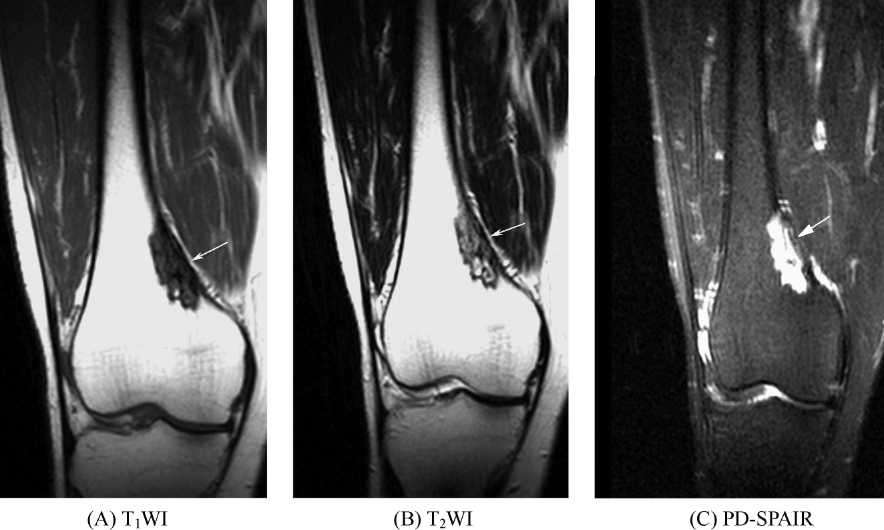

非骨化性纤维瘤分为皮质型和髓质型。皮质型多位于四肢长骨一侧皮质内或皮质下、距骺板3~4cm的干骺部,横断面呈圆形或椭圆形,突向髓腔,病变T1WI呈低信号,T2WI信号强度取决于肿瘤组织成分的含量,可为低信号、稍高信号或不均匀高信号,肿瘤髓腔侧可见半弧状更低信号硬化边,瘤周皮质可膨胀变薄或中断,无骨膜反应及软组织肿块。矢状位或冠状位可见肿瘤沿患骨长轴扩展,呈椭圆形,长径4~7cm,最长可达20cm,髓腔侧边缘硬化边多呈花边状(图2)。髓腔型少见,多位于长骨干骺端或骨端,在骨内呈中心性扩张的低信号区,侵犯骨横径的大部或全部,边缘为更低信号的硬化。

图2 非骨化性纤维瘤股骨远侧干骺端内侧皮质下可见长椭圆形骨质破坏,内部主要呈长T1稍长T2信号,并见点状短T1长T2信号及条状长T1短T2信号,边缘可见硬化缘,呈长T1短T2信号,内侧皮质略膨胀,抑脂序列可见病变呈明显高信号。